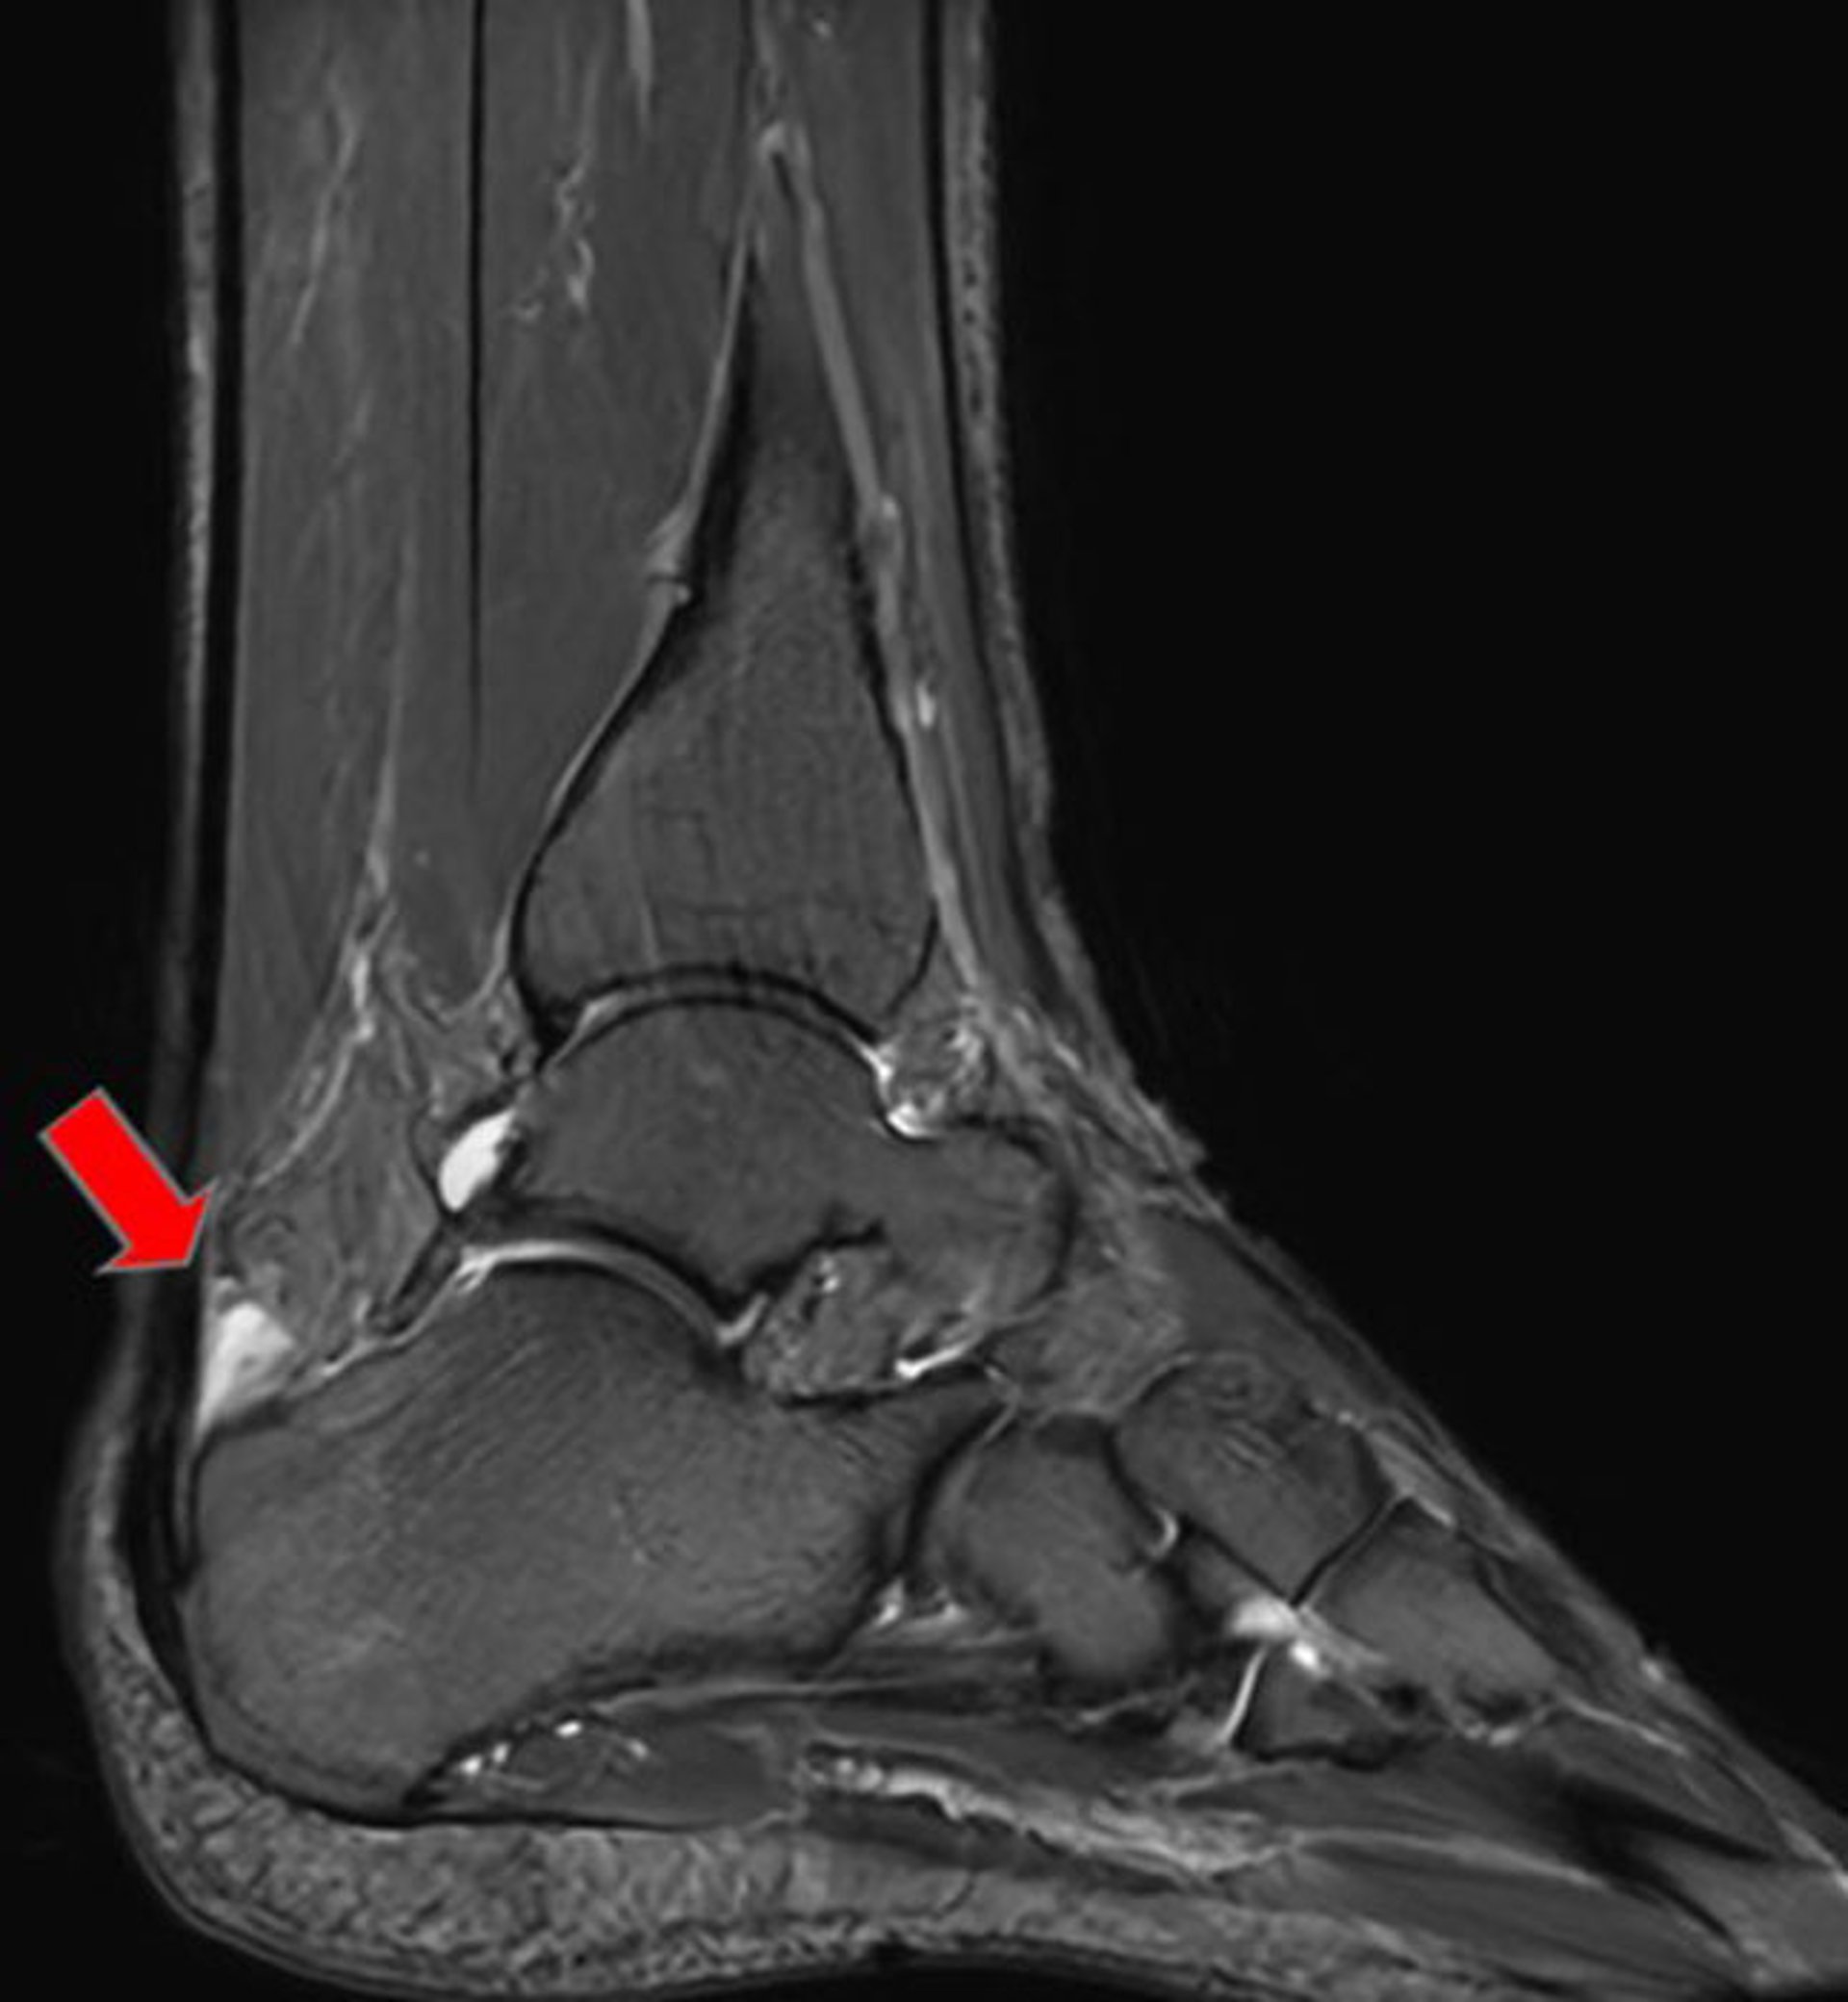

Anterior Achilles Tendon Bursa

This sagittal T2 MRI shows an anterior Achilles tendon bursa (arrow).

Image courtesy of James C. Connors, DPM.